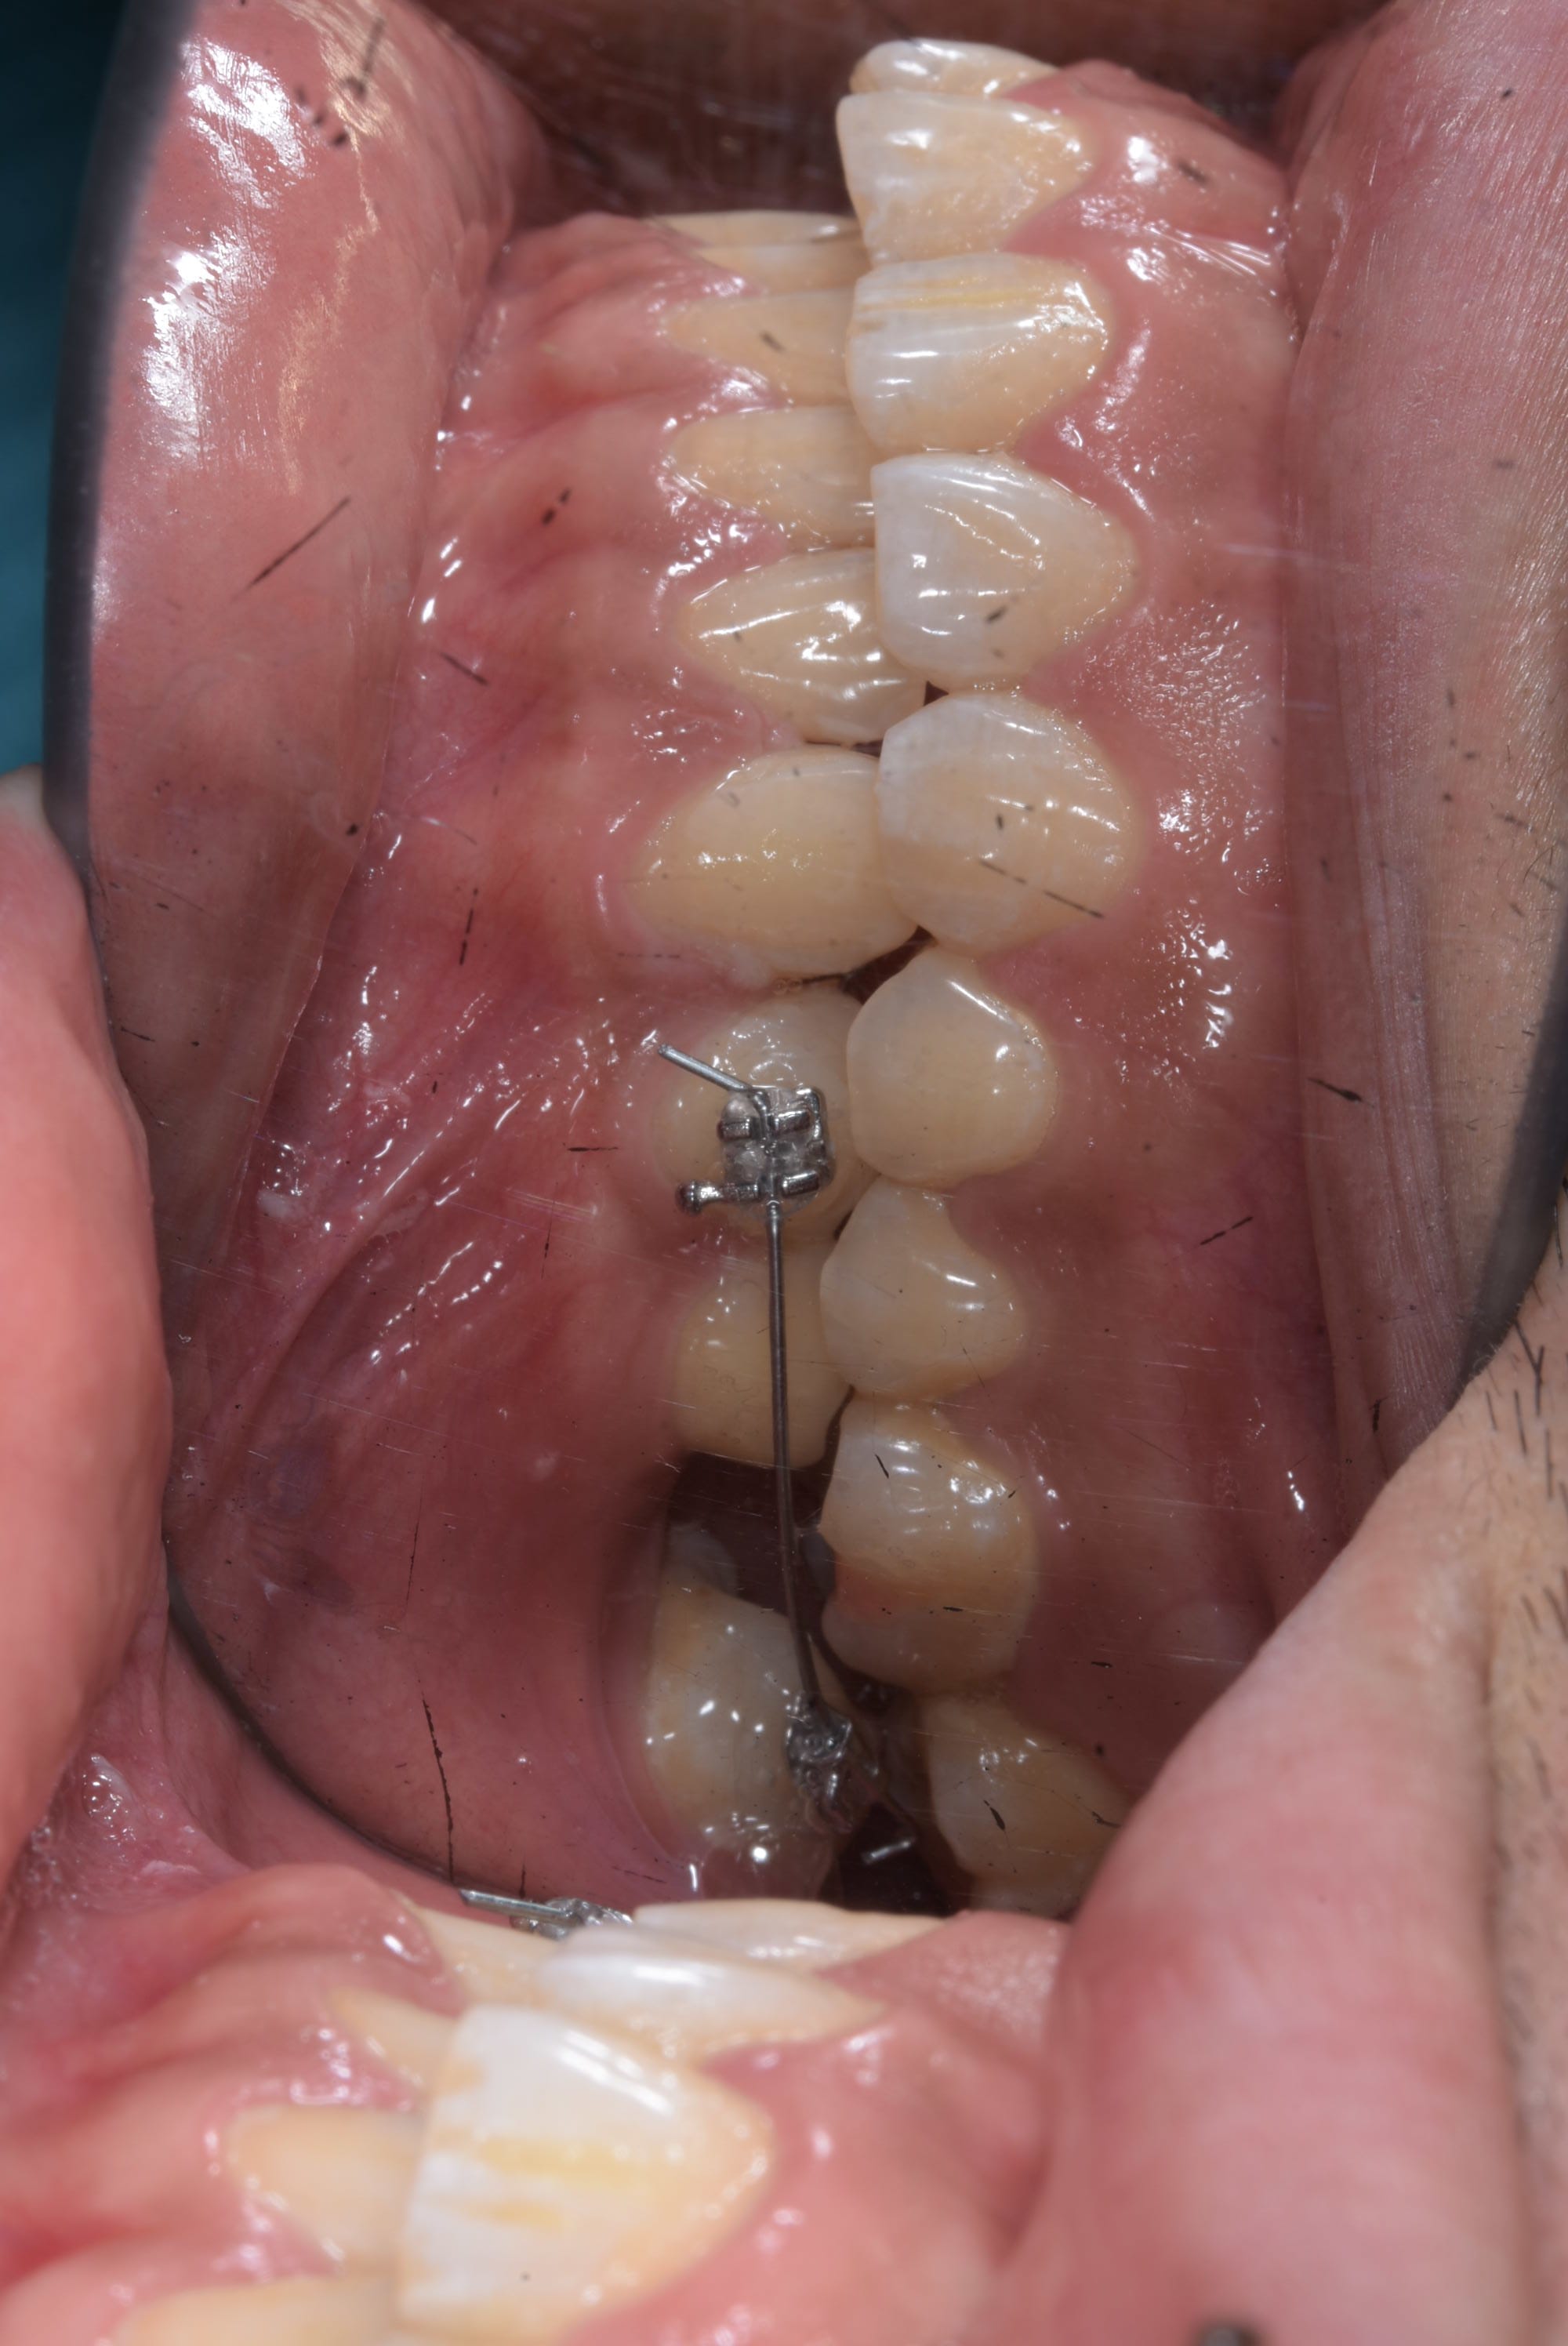

La solution :

- Prendre une empreinte alignate ( ou utiliser les modéles d'étude )

- Plier un file SS 0.02 en lingual de 45 à 33

- le fixer comme une barre de contention

- mettre un bracket sur 44 et 47

- commencer à aligner la 47 avec un file Niti.

- la molaire va vouloir s'egresser ( ici pas trop un soucie avec l'occlusion mais quand même à surveiller ) la j'ai put mettre direct un niti 18 et la semaine prochaine je devrais passer sur du niti 16 22 avec un set pour l'intrusion

J'ai mis le bracket en 45 en position apical et celui en 47 en position plus occlusal

Le file est SS 0.02 et vue que je plie mois même mes contention fixe ( en niti maintenant ) le pliage m'a prie 4 minute. J'ai collé sur le modéle en plâtre 2 minutes puis en bouche :-) . Poser les bracket m'a prit plus de temps.

Un cas qui montre la séquence

Ouverture d'espace en deux mois environ, straight wire avec un ressort. C'est con simple , efficace et relativement comfortable pour le patient